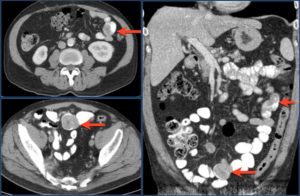

Можно выявить МТС или метастазы на УЗИ. С его помощью определяют степень развития и злокачественность онкологии. Рост, распад источника рака видно на компьютерной томографии (КТ). А также часто проявляют раковые клетки с помощью позитронно-эмиссионной томографии (ПЭТ), магнитно-резонансной томографии (МРТ), обзорной рентгенографии и радиоизотопной диагностики.

Узнать о появлении метастазов можно методами диагностики рака. К ним относится:

- биопсия;

- ультразвуковое исследование;

- компьютерная томография;

- обзорная рентгенография;

- магнитно-резонансная томография.

Методики помогают уточнить размер, характер роста, распространенность, распад и прорастание метастазов в соседние ткани и органы. Диагностика проходит в два этапа: первичное исследование и постановка диагноза, а затем обследование после лечения. Наблюдение у онколога даже после успешного проведения процедур является обязательным, потому что вероятность рецидива всегда есть.

Обзорная рентгенография, ультразвуковое исследование, радиоизотопное исследование, компьютерная томография, магнитно — резонансная томография, позитронно — эмиссионная томография, — все эти методики имеют существенное значение в распознавании метастазов.

Эти методики дают возможность уточнить величину, распространенность и характер роста метастазов, их распад, нагноение, прорастание в соседние органы и ткани.

Кроме того, эти же методики диагностики позволяют контролировать эффективность лечения по степени регресса метастазов.